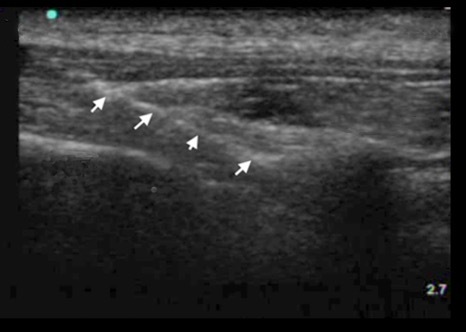

Paravertebral Transverse Intercostal Approach Image